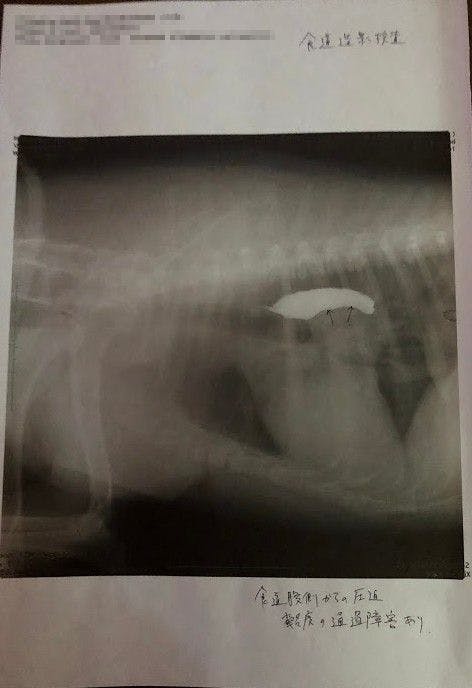

↑

バリウム飲んで検査してもらったところ、矢印の部分に腫瘍があり(白い部分は食道)、それが食道を押し上げているため、飲んだ水を吐いたりするとのことでした。(この時点で5センチほどの大きさの腫瘍でした。)

↑腫瘍の場所が体の奥のにある為、CT検査できる大学病院で検査してから手術するかどうか決めたほうがいいと言われました。

しかし段々水を吐く回数が少しずつ増えてきたのをみて、日本でも健康診断受けようと思い昨年末に動物病院で診てもらったところ、検査時で5cm程の腫瘍が体の中心(心臓近く)にあり、その腫瘍が食道を押し上げているため、飲んだ水を吐き出してしまったりしているんだろうとの事でした。